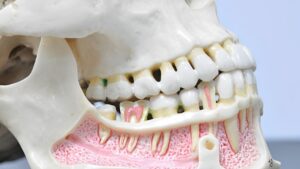

As doenças bucais são problemas comuns que podem afetar a saúde e o bem-estar de qualquer pessoa, desde cáries até doenças gengivais, essas condições podem